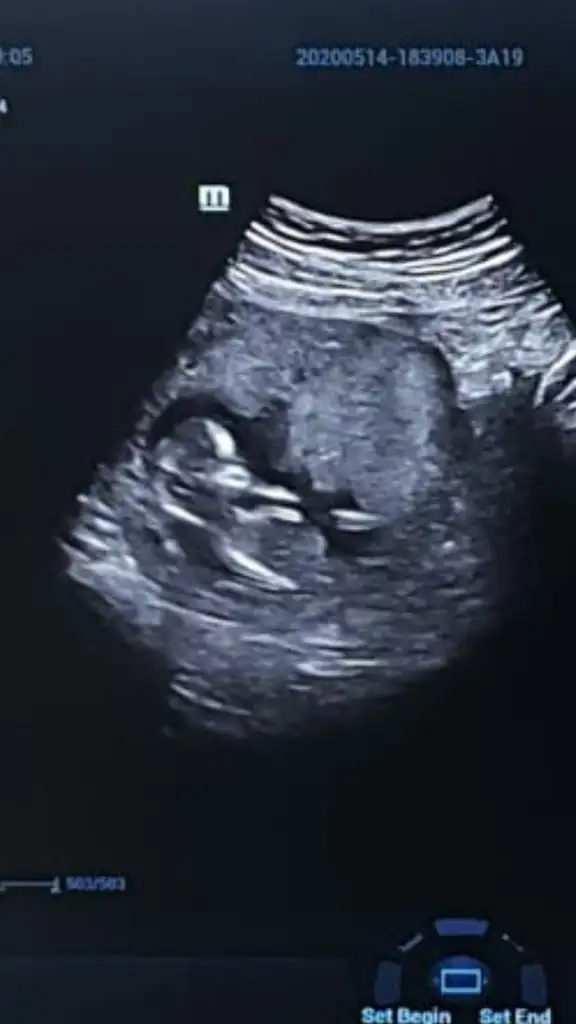

13+4 sizce kız mı erkek mi?